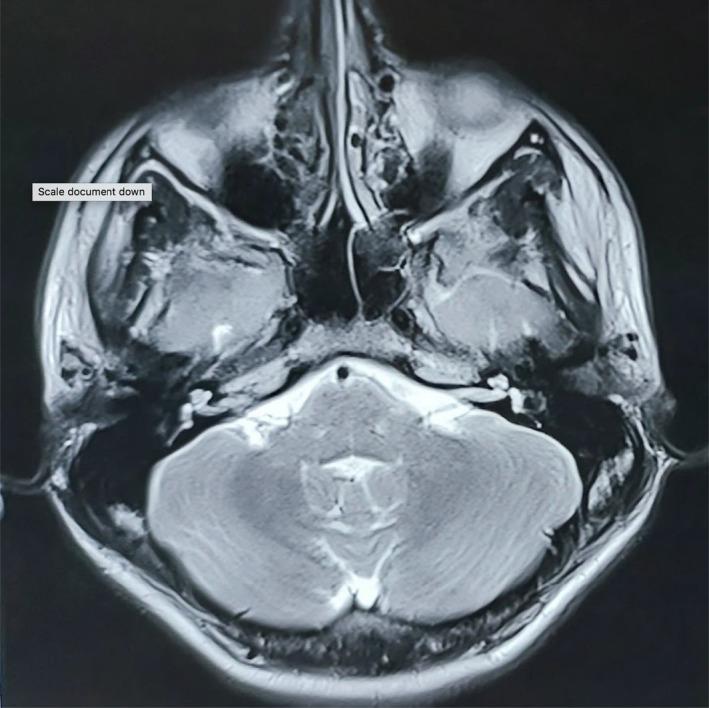

特发性红耳综合征:一例罕见病例报告。

Idiopathic red ear syndrome: A rare case report.

Red ear syndrome (RES) is a very rare disorder that is characterized by a unilateral or bilateral attack of paroxysmal burning sensation and reddening of the external ear. The duration of symptoms ranges from a few seconds to hours. It can occur spontaneously or be triggered by rubbing of the ear, heat or cold stimulation, brushing of hair, and neck movement. Diagnosis and treatment of this condition are challenging. The pathophysiology of RES is still unclear and hypotheses involving peripheral or central nervous system mechanisms have been proposed. RES is regarded as refractory to medical treatments, although some migraine preventative treatments have shown moderate benefit mainly in patients with migraine-related attacks. We report a case with Idiopathic RES who presented with paroxysmal redness of the bilateral pinnae partially benefitted by medical treatment.

摘要

红耳综合征(RES)是一种非常罕见的疾病,其特征为单侧或双侧耳部阵发性烧灼感和外耳发红。症状持续时间从几秒到数小时不等。它可自发出现,也可由揉耳、热或冷刺激、梳头及颈部运动诱发。该病症的诊断和治疗具有挑战性。RES的病理生理学仍不清楚,有人提出了涉及外周或中枢神经系统机制的假说。尽管一些偏头痛预防性治疗主要对偏头痛相关发作的患者显示出一定益处,但RES被认为对药物治疗无效。我们报告一例特发性RES患者,其双侧耳廓阵发性发红,经药物治疗后部分好转。